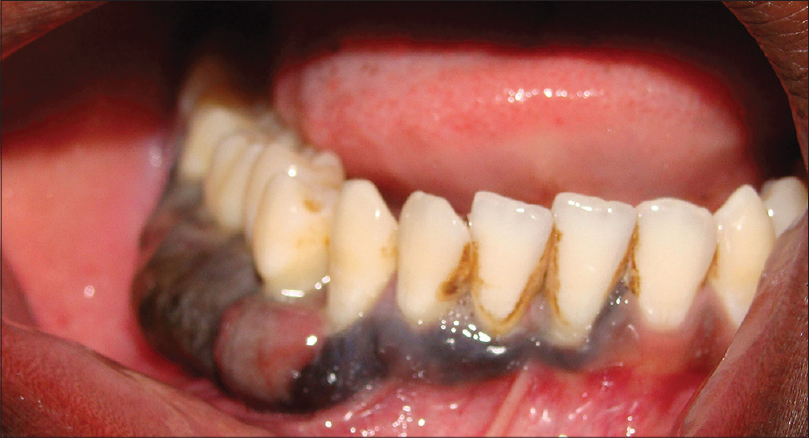

Si encontraste una anomalía en tus encías, paladar, dientes o labios, es necesario acudir a examinarte la lesión, evitando que esta se desarrolle y avance a más complicaciones en el futuro. La principal razón de las alteraciones de la encía son las bacterias, pero hay que saber que existen lesiones que son la manifestación de problemas que se pueden detectar cuando están iniciando y que se relacionan con enfermedades dermatológicas, con las hormonas, medicamentos, virus, hongos, discrasias sanguíneas, alteraciones oncológicas o, genéticas.

Estas patologías se pueden manifestar como lesiones blancas, lesiones rojas, ulceraciones o, tumoraciones.